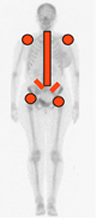

También puede encontrarse compromiso de articulaciones periféricas, de forma bilateral y con mayor frecuencia en las caderas y los hombros. (Fig 56 A).

Fig 56 A. Distribución de la espondilitis anquilosante.

Siempre compromiso de sacroiliacas y todos los segmentos vertebrales.